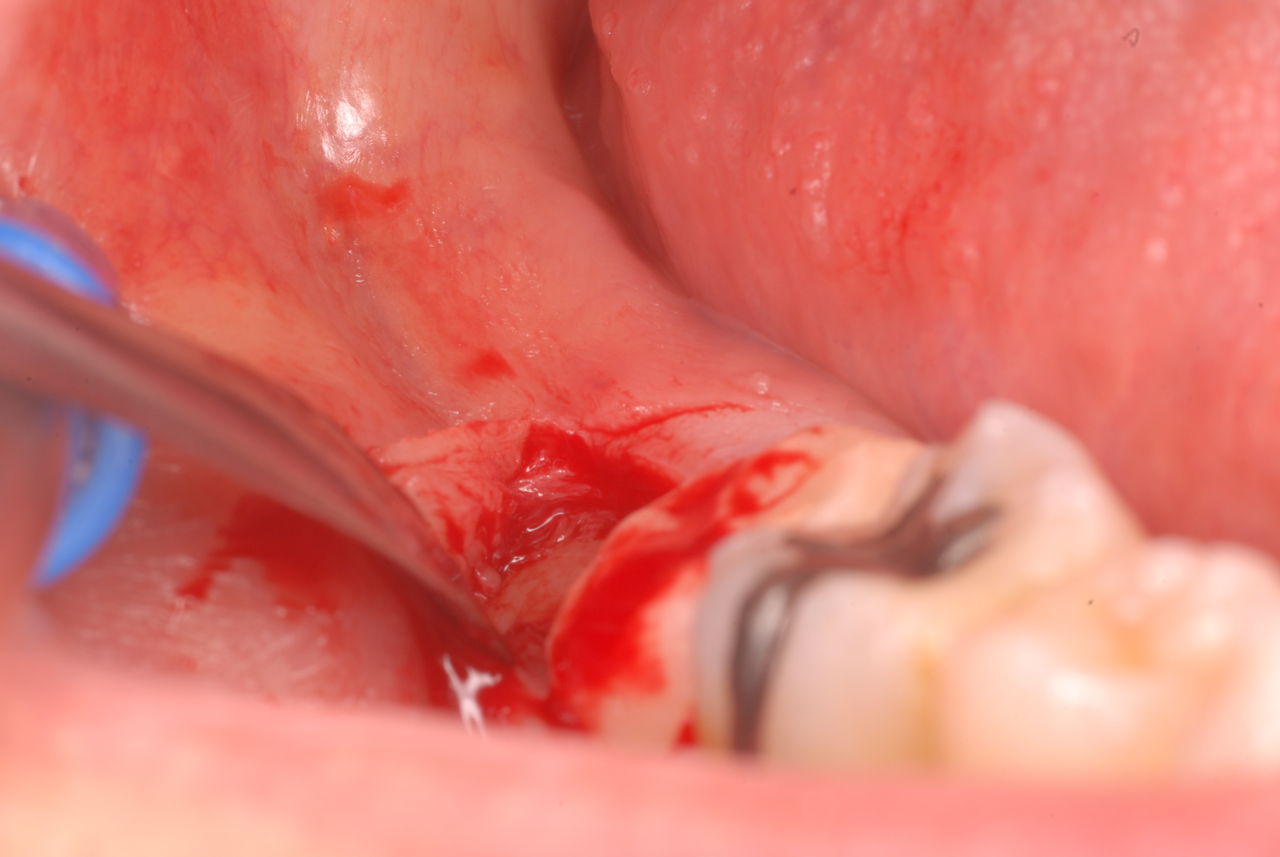

下記は患者に言われるままに血だらけでの不潔な状態で虫歯をとり埋めたようで全然適合していませんし、外れそうになっていました。

外したところです。中は虫歯のオンパレードでした。

適合が悪い銀歯が装着されていて更に虫歯の取残しにより歯髄炎症を起こして神経を取らざるをえなくなりました。神経を除去すれば痛みはなくなります。でもそれは死ぬことなのです。ほぼ寿命は半減したと考えるしかないのです。